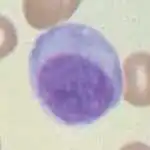

Micrograph of a plasma cell with distinct clear perinuclear region of the cytoplasm, which contains large numbers of Golgi bodies. | |

Plasma cells are large lymphocytes with abundant cytoplasm and a characteristic appearance on light microscopy. They have basophilic cytoplasm and an eccentric nucleus with heterochromatin in a characteristic cartwheel or clock face arrangement. Their cytoplasm also contains a pale zone that on electron microscopy contains an extensive Golgi apparatus and centrioles. Abundant rough endoplasmic reticulum combined with a well-developed Golgi apparatus makes plasma cells well-suited for secreting immunoglobulins.[4] Other organelles in a plasma cell include ribosomes, lysosomes, mitochondria, and the plasma membrane.